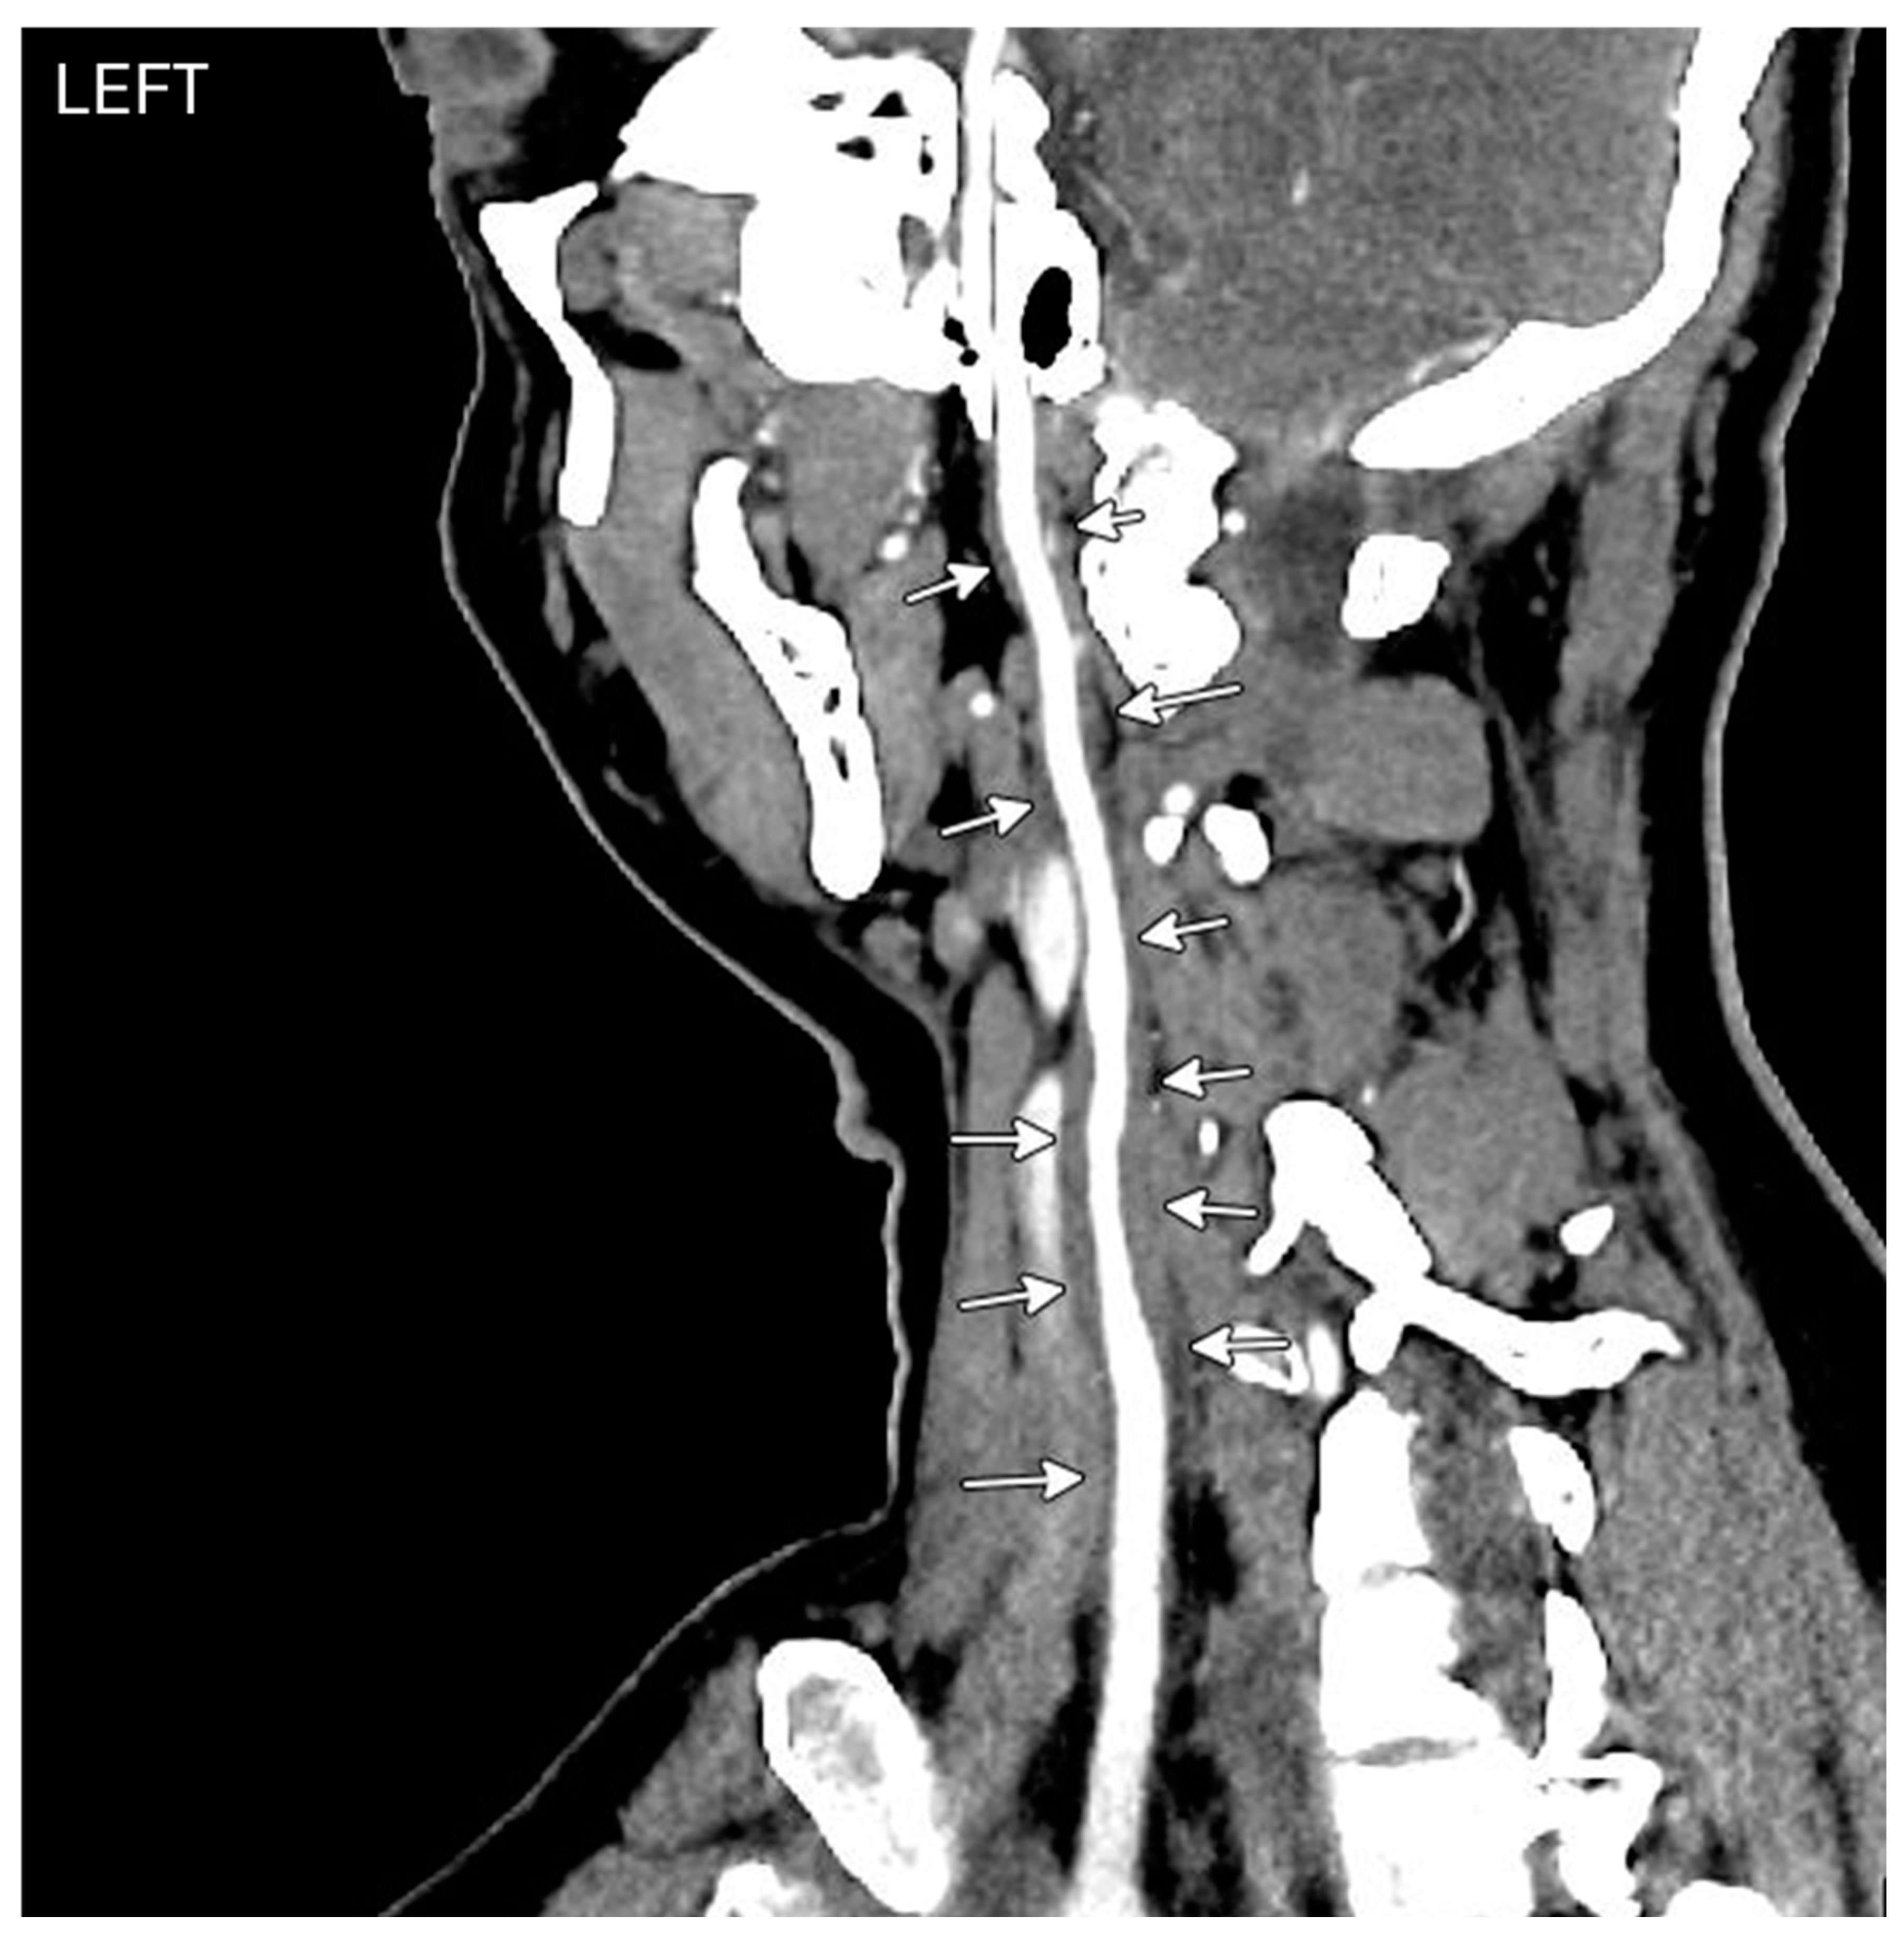

Figure 1. OS Fundus phorograph showing Central retinal artery occlusion with characteristic cherry red spot and attenuated blood vessels. Patient developed left central retinal artery occlusion years prior to the vasculitis diagnosis with loss of vision at a young age.

A 35-year-old woman with a prior history of left central retinal artery occlusion and bilateral sensorineural hearing loss concerning initially for neurosarcoidosis (never histologically proven) presented for clinic follow-up. She had a complicated disease course dating back many years involving different specialists including fluctuating hearing loss partially responsive to corticosteroids necessitating cochlear implants and developed central retinal occlusion of the left eye (Figure 1 and Figure 2). This was concerning for possible underlying inflammatory condition such as neurosarcoidosis or Susac syndrome (MRI atypical sans corpus lesion) and she received IV immunoglobulin treatment. When she returned for follow-up, she had complaints of episodes of confusion, but quiescent symptoms without visual change, status post adalimumab and methotrexate addition. She sought emergency care for new transient arm numbness and confusion and CTA neck revealed carotid bulb circumferential thickening suggestive of vasculitis (Figure 3, Figure 4 and Figure 5). The patient was initiated on Infliximab with IV methylprednisolone and close follow-up with neurology and vascular medicine for management of Takayasu arteritis.